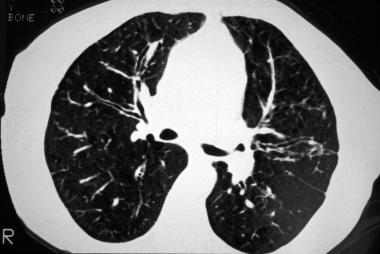

?支气管扩张:支气管扩张是最常见的CT异常 , 约80%的患者可见支气管扩张 , 可见柱状型、曲张型和囊状型扩张 。

图8 显示支气管壁增厚及“轨道征” , 主要在上叶

图9 可见“葡萄串征”

图10 可见支气管周围的磨玻璃样浑浊及过度充气

图11 CF及急性胸痛患者的CT显示柱状型及囊状性支气管扩张 , 以及右上叶的空隙和皮下气肿 。 气胸是出现囊肿时的常见并发症 。